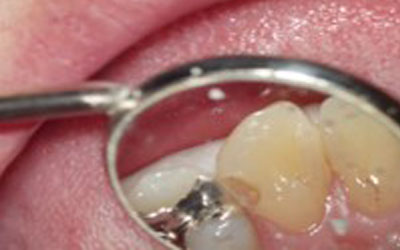

歯は小さくその中にできる虫歯はさらに小さいです。今までは、歯科医師の熟練度により『勘』で虫歯を取っていましたが、拡大することにより、確実に虫歯や細菌を除去することが出来るようになりました。

虫歯が大きいため今までなら神経の治療になるような虫歯でも、顕微用を使い虫歯のみを除去することで、神経の治療を避けることができる場合もあります。